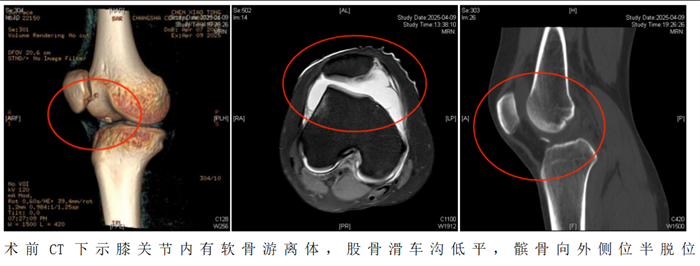

“患者入院后,我们为她制定了周密的个性化治疗方案,采用‘关节镜下髌骨成形术+纽扣十字缝合法软骨修复术’帮助恢复膝关节功能。”据91短视频 (南华大学附属长沙中心医院)运动医学、创伤关节、骨病科主任丑克介绍,这项联合术式在省内少见,因患者游离软骨骨碎片大,软骨下骨骨质有血运,髌骨内下缘软骨缺损面积大,通过高强度缝线采用纽扣十字缝合法原位缝合剥脱的软骨块成形髌骨,犹如为膝关节打造了一个防护网。手术过程顺利,术后患者恢复良好。

2.如果出现以下情况需要考虑手术治疗。初次脱位后出现髌骨或股骨软骨骨折导致关节内出现游离体时,必须手术治疗。关节镜是目前成熟的关节内镜技术,医生通过内镜,直视下观察髌骨的损伤,取出游离体并修复软骨,行内侧支持带紧缩和外侧支持带松解术,即可取得满意的疗效。该手术是微创手术操作,创伤小,恢复快,多数患者术后第1天即可下地活动。